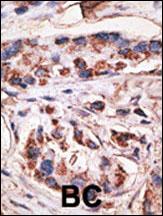

Formalin-fixed and paraffin-embedded human cancer tissue reacted with the primary antibody, which was peroxidase-conjugated to the secondary antibody, followed by DAB staining. This data demonstrates the use of this antibody for immunohistochemistry; clinical relevance has not been evaluated. BC = breast carcinoma; HC = hepatocarcinoma.